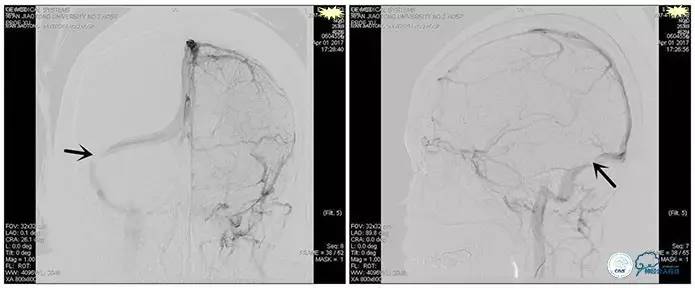

术中造影

术后造影

狭窄较前有改善

术中测压

远端压力:530mmH2O

近端压力:120mmH2O